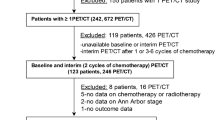

Of 65 patients who fulfilled the inclusion criteria, seven were excluded at baseline due to elevated blood glucose levels (>150 mg/dL). Thus, a total of 58 patients (28 women and 30 men; mean age 58.9 ± 17.6 years, range, 25–92 years) fulfilled the criteria for participation in the study. Of these 58 patients, 11 were diagnosed with HL, 25 with DLBCL (15 in the R-CHOP arm, and 10 in the DA-EPOCH-R arm), 12 with FL, and 10 with MCL. One patient with FL and one patient with MCL underwent [18F]FDG PET/MR at baseline and FU-1, but not at FU-2; whereas one patient with DLBCL (R-CHOP arm) underwent [18F]FDG PET/MR at baseline and FU-2, but not at FU-1. A total of 166 target lesions (134 nodal, 32 extranodal; Table 1) were analysed.